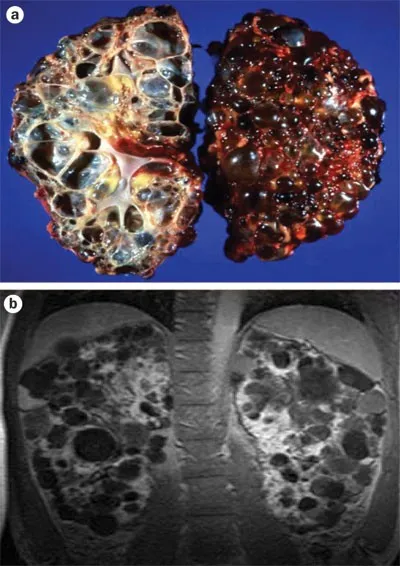

Polycystic Kidney Disease - A Tale of Two Cysts

A comparison of the two major forms of polycystic kidney disease:

| Feature | Autosomal Dominant (ADPKD) | Autosomal Recessive (ARPKD) |

|---|---|---|

| Inheritance | Autosomal Dominant | Autosomal Recessive |

| Gene Defect | PKD1 (85%), PKD2 | PKHD1 (Fibrocystin) |

| Onset | Adulthood (20-40 yrs) | Infancy / In utero |

| Presentation | Hypertension, hematuria, flank pain, palpable bilateral masses | Potter sequence, renal failure in infancy, hypertension, portal HTN |

| Extrarenal | Hepatic cysts (>50%), Berry aneurysms, Mitral Valve Prolapse | Congenital Hepatic Fibrosis, Biliary Dysgenesis |